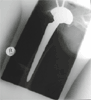

Post

Op

total hip replacement thru minimally invasive single incision

Progress

Patient wih good pain relief and hip motion